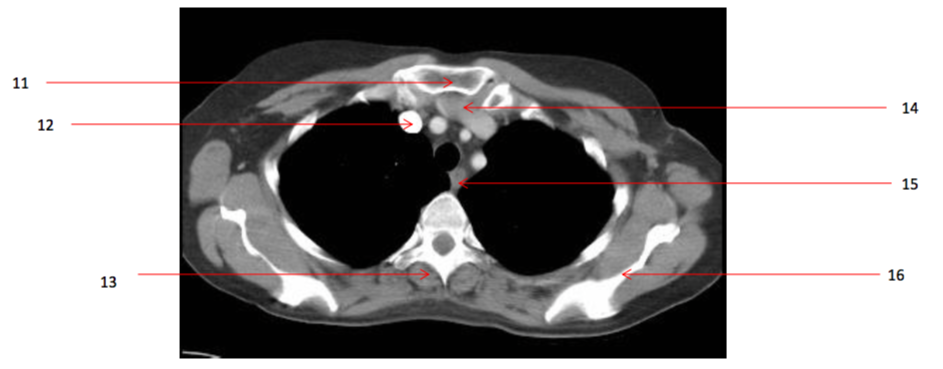

17

Number 11?

A

15

Number 14?

Lt brachiocephalic vein

13

Number 16?

Lt scapula

14

Number 33?

43

Number 15?

oesophagus